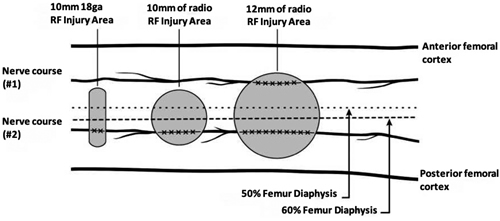

Before deepening the RF of GN, let us remember the basic principles of this technique. The RF signal produces two types of fields at tissue level: An electrical field and a magnetic field. At 500 KHz a magnetic field is negligible, the electric field being the source of all the effects observed in the injury produced by RF. The electric field produces forces in ions and other electrically charged structures, generating ionic movements, electrical currents, stress of membranes and cellular substructures. The generated current produces ionic friction, heat and temperature rise, producing nerve destruction above 45 °C. All these mechanisms, and not just the increase in temperature, have the potential to produce structural changes in the architecture of the nerve when the electric field is high enough (6). It is also important to know the factors that modify the size and shape of the lesion generated by RF, within which we find: Diameter of the needle, temperature reached, duration of the thermal radiofrequency (TRF), length and proximity of the active tip of the electrode to the target tissue (7,8).

The size of the lesion generated by TRFGN depends not only on the distance we are at from the nerve, but also on the duration of the TRF, the set temperature and the length of the active tip. No standardization of parameter is found in studies using TRFGN, for example, the length of the active tip varies between 5 mm and 10 mm, the temperature between 60 ºC and 80 °C and the duration of the procedure varies between 90 seconds and 270 seconds. This variability can lead to changes in clinical outcomes and long-term effectiveness of TRF (26). Future clinical trials should investigate which are the ideal parameters.

It is worth noting that the clinical improvement is greater in studies that have been performed with cooled radiofrequency (CRF) (22,35), probably because of the larger size of the spherical lesion generated by the CRF needle that could involve a larger number of sensitive branches (Figure 5). Indeed, Tran et al. (13) proposed to perform techniques with bipolar TRF based on their anatomy studies, where not only an ablation of the sensitive branches of the SMGN and SLGN is performed, but also of the medial and lateral branches of the VIN. In our review we found only one study comparing monopolar and bipolar TRF, without showing differences in the duration of pain relief (36).

Fig. 5. The three most commonly used sizes of radiofrequency (RF) lesions (thermal RF. Bipolar RF. Cooled RF). Image obtanied from Franco et al. (10). Reproduced with the authorization of Carlo D. Franco.